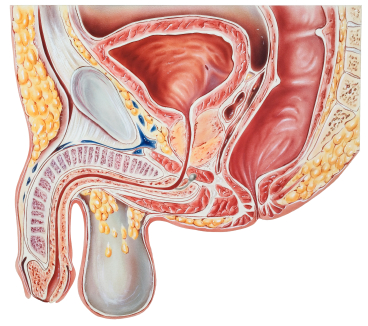

Орхит-это воспаление яичка.Процесс воспаления редко возникает внезапно,на фоне полного здоровья.Чаще всего это осложнение инфекционного процесса(грипп,тиф,паротит,туберкулез,простатит,уретрит и т.д) и поражает только одно яичко.

О.бывает специфическим(при инфекционных заболеваниях поражающих железистую ткань,например-паротит),неспецифическим,асептическим(при травме яичка)

По течению О.может быть острым и хроническим.

Острый О.дифференцируют от острого эпидидимита,ущемления паховой грыжи, водянки яичка,заворота яичка. Хронический О. нуждается в дифдиагностике с опухолью яичка. Для этого используют исследования :ультразвуковое ,радионуклидное исследования, цитологический пунктат яичка.